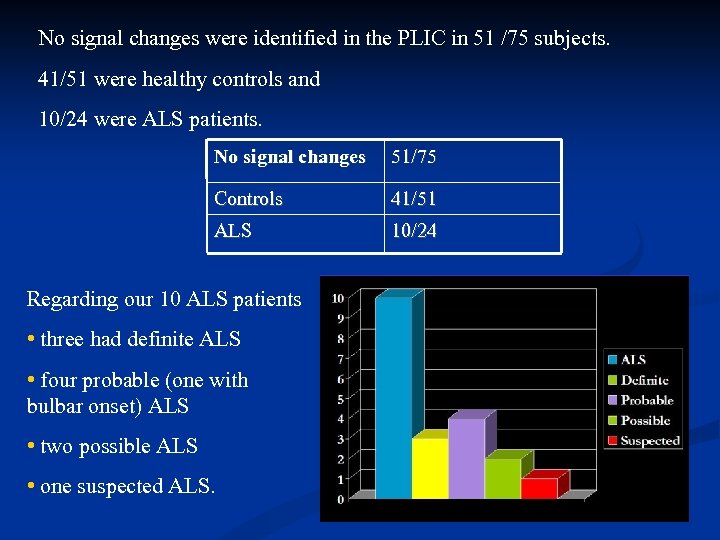

No signal changes were identified in the PLIC in 51 /75 subjects. 41/51 were healthy controls and 10/24 were ALS patients. No signal changes 51/75 Controls 41/51 ALS 10/24 Regarding our 10 ALS patients • three had definite ALS • four probable (one with bulbar onset) ALS • two possible ALS • one suspected ALS.

No signal changes were identified in the PLIC in 51 /75 subjects. 41/51 were healthy controls and 10/24 were ALS patients. No signal changes 51/75 Controls 41/51 ALS 10/24 Regarding our 10 ALS patients • three had definite ALS • four probable (one with bulbar onset) ALS • two possible ALS • one suspected ALS.